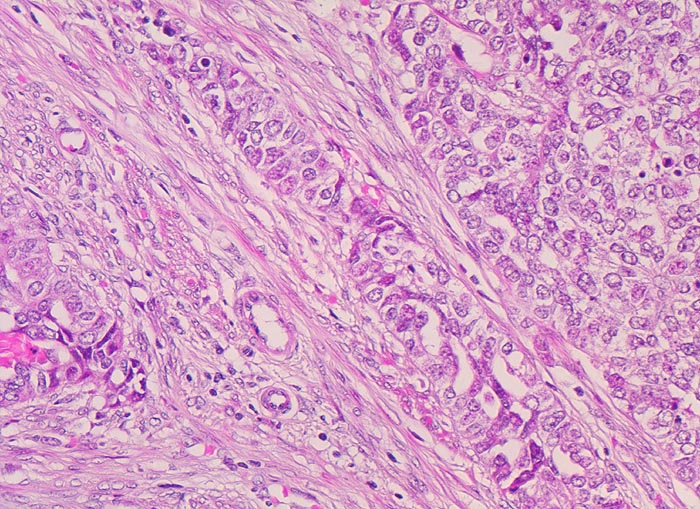

Morphologische Merkmale:

• Endomyometranes Gewebsfragment.

• Die rechte Seite des Uteruskavums wird ausgekleidet von flachem atrophem Endometrium. Im Cavum liegt ein Blutkoagel mit nekrotischem Detritus nach vorausgegangener diagnostischer Utersukurettage.

• Anstelle des Endometriums findet sich in der linken Hälfte des Uteruskavums ein Adenokarzinom bestehend aus architektonisch komplexen Drüsen. Die Drüsen liegen teils dos à dos ohne erkennbares Stroma zwischen zwei Drüsenschläuchen.

• Tumorzellverbände infiltrieren die glatte Muskulatur des Myometriums.

• Tumordrüsen ausgekleidet von mehrreihig angeordneten Tumorzellen mit hyperchromatischen polymorphen längsovalen Tumorzellkernen mit zahlreichen Mitosen. Die Morphologie der Tumordrüsen erinnert an proliferatives Endometrium.

• Anmerkung: Typischerweise ist das endometrioide Karzinom des Uterus als Folge des ursächlichen Hyperöstrogenismus assoziiert mit einem hyperplastischen Endometrium (siehe Präparat 148). Im Kurspräparat erscheint hingegen das nicht-neoplastische Endometrium nach vorausgegangener Kurettage atroph. Atrophes Endometrium findet sich sonst charakteristischerweise neben serösen Endometriumkarzinomen postmenopausaler Patientinnen. Das sollte der Kliniker dem Pathologen mitteilen: